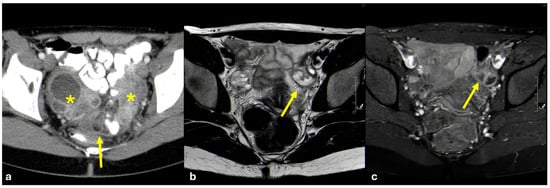

3.3.5. Pelvic Inflammatory Disease

- Foti, P.V.; Tonolini, M.; Costanzo, V.; Mammino, L.; Palmucci, S.; Cianci, A.; Ettorre, G.C.; Basile, A. Cross-sectional imaging of acute gynaecologic disorders: CT and MRI findings with differential diagnosis-part II: Uterine emergencies and pelvic inflammatory disease. Insights Imaging 2019, 10, 118. [Google Scholar] [CrossRef]

- Sam, J.W.; Jacobs, J.E.; Birnbaum, B.A. Spectrum of CT findings in acute pyogenic pelvic inflammatory disease. Radiographics 2002, 22, 1327–1334. [Google Scholar] [CrossRef]

- Tukeva, T.A.; Aronen, H.J.; Karjalainen, P.T.; Molander, P.; Paavonen, T.; Paavonen, J. MR imaging in pelvic inflammatory disease: Comparison with laparoscopy and US. Radiology 1999, 210, 209–216. [Google Scholar] [CrossRef]